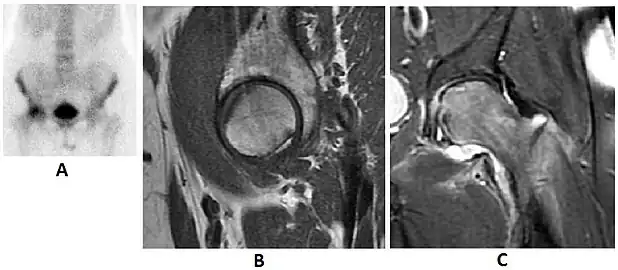

Figure 8:

-

X-ray of a patient with transient osteoporosis of the left hip showing osteoporosis.[1] -

Coronal stir imaging in transient osteoporosis, showing diffuse edema.[1] -

Scintigraphy (A), sagittal T1 (B), and coronal PD fat sat of a patient with a subchondral fracture of the femoral head with convex shape to the articular surface.[1] -

Coronal T1 of a patient with avascular necrosis of the femoral head.[1]